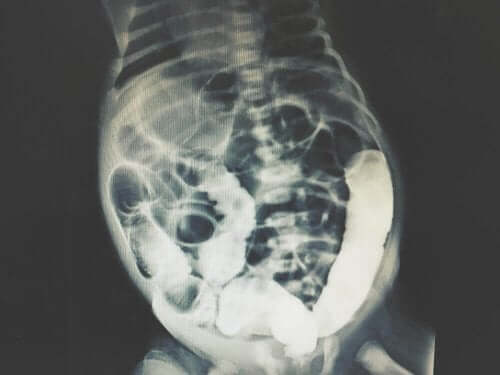

腹腔洗浄で、信頼性の高い健康診断を得ることができます。さらに、誤検知やその他のエラーが最小限に抑えられます。医者は通常、他の医療診断画像とともに腹腔洗浄を行い、CT(コンピューター断層撮影)スキャンまたはMRI(磁気共鳴画像)として実行します。

結果に応じて、専門家チームは腹部の問題の原因を特定します。また、腹部の内部画像を取得するための検査を実施することもあります。これにより、診断が容易になるのです。